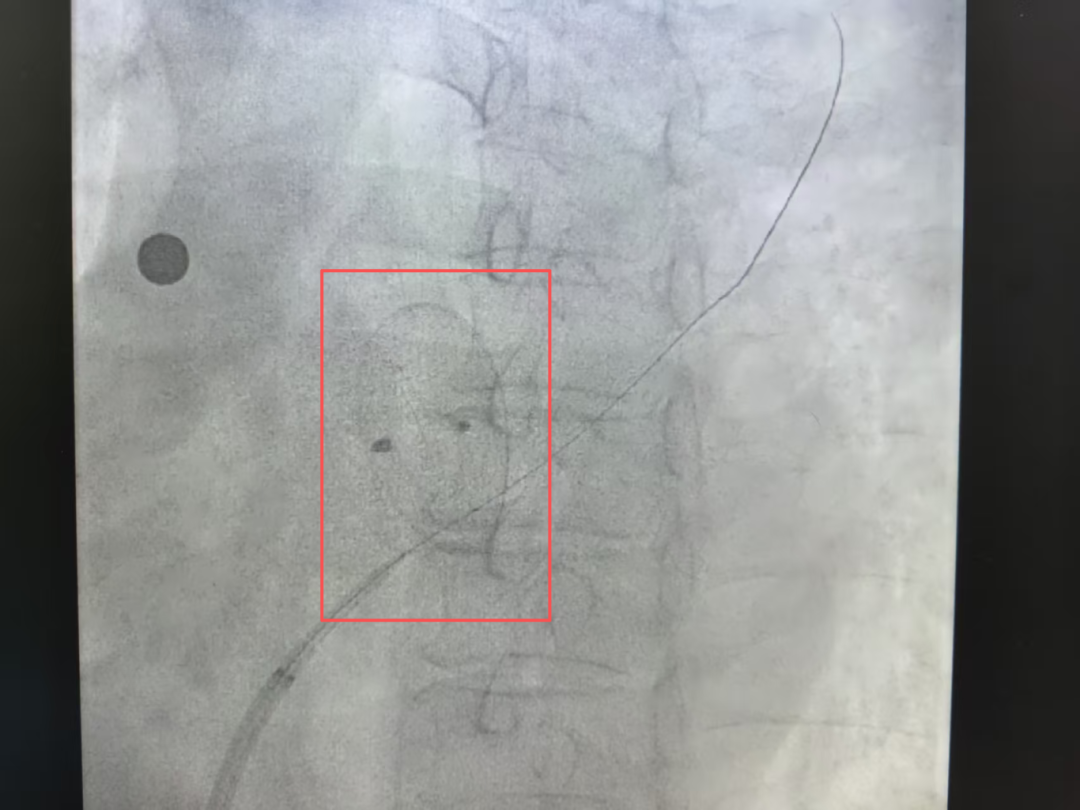

在x光二维影像的精准导航下,导丝尖端不是暴力穿刺,而是在封堵器的金属网格间精巧地“探”寻、“绕”行,最终成功穿透一个天然的网眼,完成了初始通道零的突破。

纤细的导丝成功穿透封堵器(红框处)